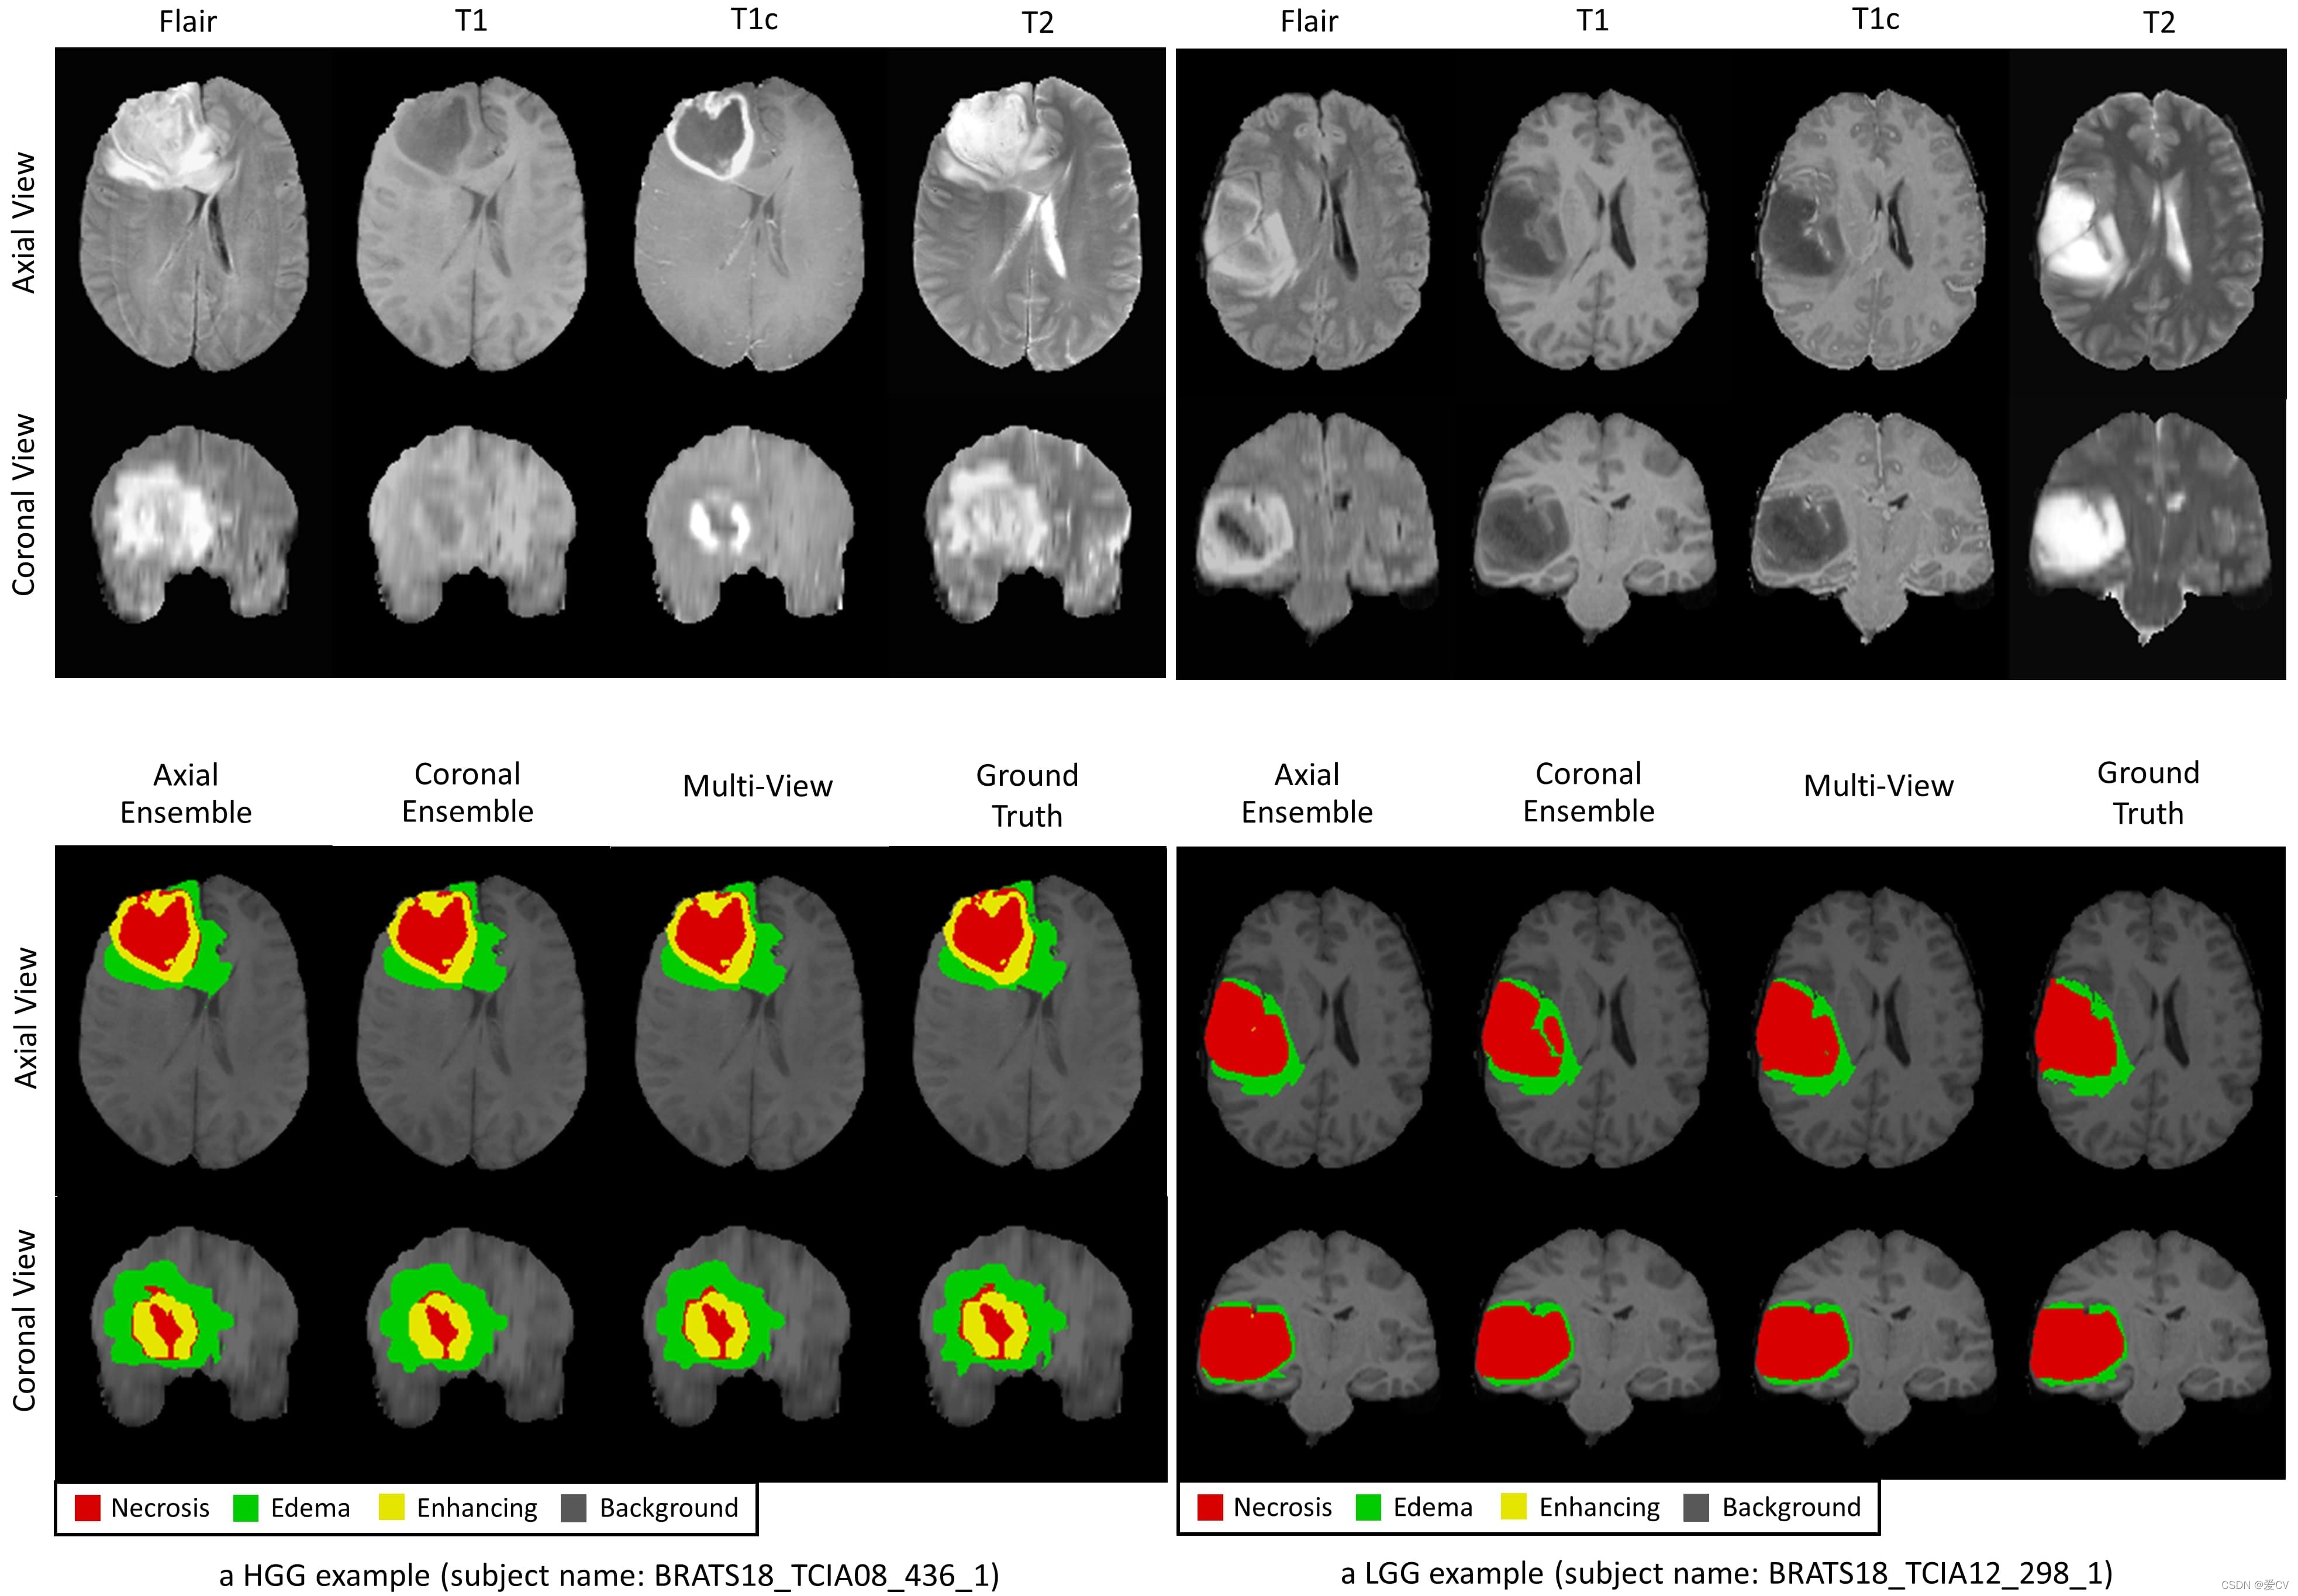

数据集来源于BraTS2018平台(链接:https://www.med.upenn.edu/sbia/brats2018.html),主要用于医学图像分割;

训练过程中从3D MRI中提取2D切片并构建3D预测图以提高效果;

为了从 MRI 的三维数据中获取二维切片。通过分析三维图像数据来识别和分割感兴趣区域,在测试阶段我们采用连接多张2D预测图的方法构建完整的3D输出体积。为了提高结果的一致性与准确性,在最终输出阶段我们将不同视角的数据进行融合得到预期效果。

结果

研究结果基于 BraTS 2018 验证集来自 BraTS 在线评估平台。